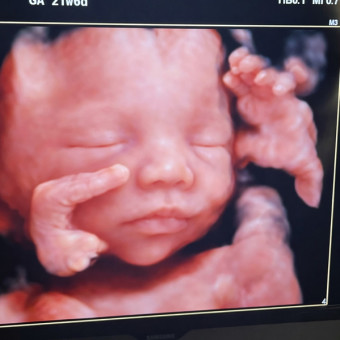

Mateo’s Baby Registry

H. Minnich & M. Minnich

Smyrna, TN

April 25, 2026